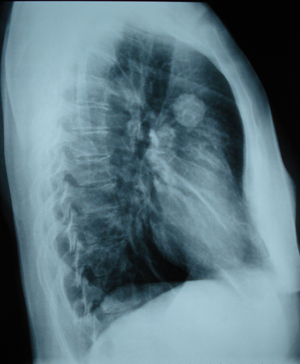

Εικόνα 2

Πλάγια ακτινογραφία θώρακος. Στρογγυλή σκίαση πάνω από το επίπεδο της πύλης στο πρόσθιο τμήμα του άνω λοβού.